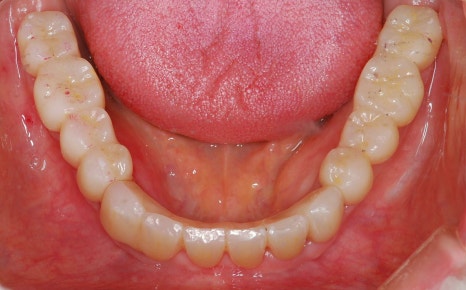

무치악환자를 위한 전악임플란트

전악임플란트 중점 치료

<참고이미지> 무치악 환자의 임플란트 치료 사례 / 환자에 따라 치료결과는 다를 수 있으며 임플란트 주위염 등이 발생할 수 있습니다.

무치악 환자에게 적용시 치아의 기능을 일정수준으로 회복할 수 있는 치료입니다.

20.09.19 경과체크 / 무치악 임플란트 치료 / 환자에 따라 치료결과는 다를 수 있으며 임플란트 주위염 등의 부작용이 발생할 수 있습니다.

기능의 회복은 물론 심미적인 목적도 충족 시킬 수 입니다.